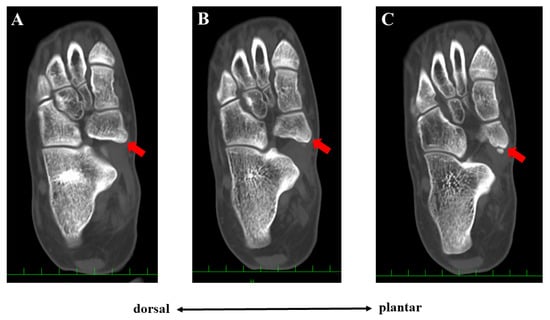

2. Case Presentation